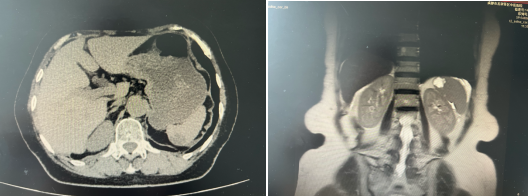

术前影像